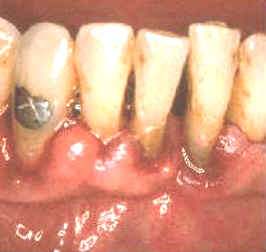

La imagen muestra como quedan las lesiones después

de 14 días del tratamiento. El paciente ha realizado enjuagatorios de

un minuto de duración con

10 ml de chlorhexidine al 0.2% dos veces al día. |

Además ha

mejorado su habilidad para cepillar sus dientes. Los dientes están

relativamente libres del

placa dental pero se han manchando

por el clohexidine en las áreas proximales. Los tejidos blandos se

encuentran sanos y aumentaron su firmeza, (resistencia al sondaje) y hay

muy pocas zonas que sangran al sondaje. |

El caso ilustrado demuestra la capacidad del

tejido gingival de sanar cuando se elimina la placa, cemento y dentina infectados y

cálculos. La curación es muy rápida si el paciente coopera con una

buena higiene dental. En este caso particular

el cambio es dramático. |